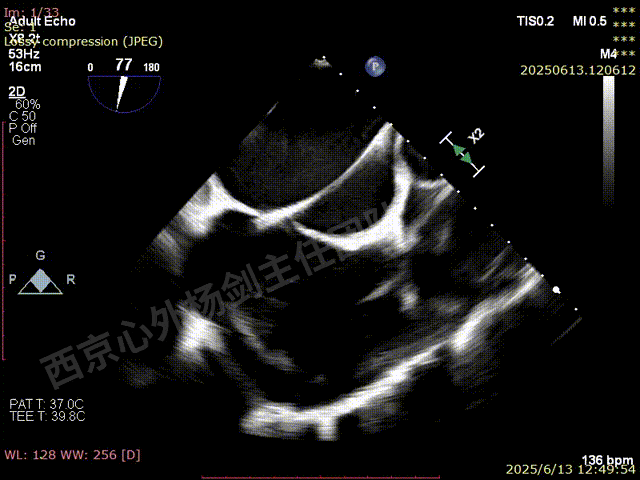

房间隔穿刺,最终高度4.5cm

超声引导下,扩张器螺纹组织及等号标记依次通过房间隔

第一枚XTW在2区弹道测试调整

第一枚XTW打开确认orientation,穿刺位置良好无需调整hug

XTW进入瓣下,以较小的角度先捕捞后叶

反复尝试,瓣叶卷曲,前后瓣叶不明确

捕捞完成后确认orientation,gripper down

夹子关闭后检查夹子两侧反流

第一枚XTW释放后评估,外侧反流基本消失,内侧仍然有中度以上反流

第二枚XT于第一枚夹子内侧瓣上调整

第二枚XT关闭后评估,trace

二尖瓣平均跨瓣压差1mmHg

释放后评估,反流降至1+,组织桥稳定